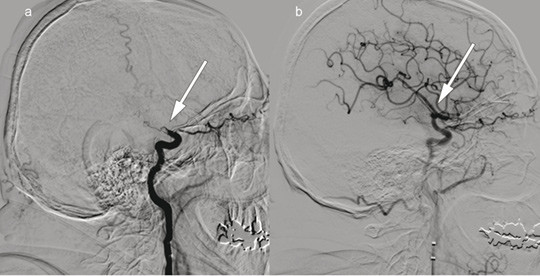

Pasient 1. En mann i 70-årene ble innlagt på grunn av akutt oppståtte høyresidige lammelser. Nevrologiske utfall ble skåret med National Institutes of Health Stroke Scale (NIHSS) til 21 poeng (alvorlig hjerneinfarkt), og intravenøs trombolytisk behandling ble gitt. Bildet til venstre viser cerebral angiografi med kontrastinjeksjon i venstre a. carotis interna, a) før og b) etter embolektomi av en såkalt T-okklusjon (piler) i venstre carotissifongen og a. cerebri media. Tromben ble fjernet og blodstrømmen til venstre hemisfære gjenopprettet etter 195 minutter fra ictus. Utredning viste atrieflimmer og embolisk hjerneinfarkt i a. cerebri medias forsyningsområde. Pasienten fikk antikoagulasjonsbehandling med rivaroksaban. Ved kontroll etter tre måneder var NIHSS-skåren 0 poeng.